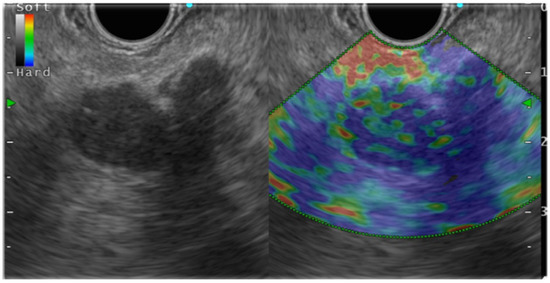

In general, EUS-EG shows pancreatic ductal carcinoma as a heterogeneous blue color because it is harder than the surrounding pancreatic parenchyma (Figure 3). Pancreatic endocrine tumors (P-NET), portrayed as blue, are homogeneous and harder than the surrounding pancreatic parenchyma. Mass-forming pancreatitis, having lower hardness than the surrounding area and heterogeneity, is shown as green. However, as chronic pancreatitis-like changes become more intense, the lesions become heterogeneous with higher hardness (blue color) than the surrounding areas, which might make it difficult to distinguish such lesions from pancreatic cancer. Numerous reports have described studies demonstrating the usefulness of EUS-EG for PSL (Table 2, Table 3 and Table 4).

Figure 3.

Endosonography(EUS) elastography in pancreatic ductal carcinoma.